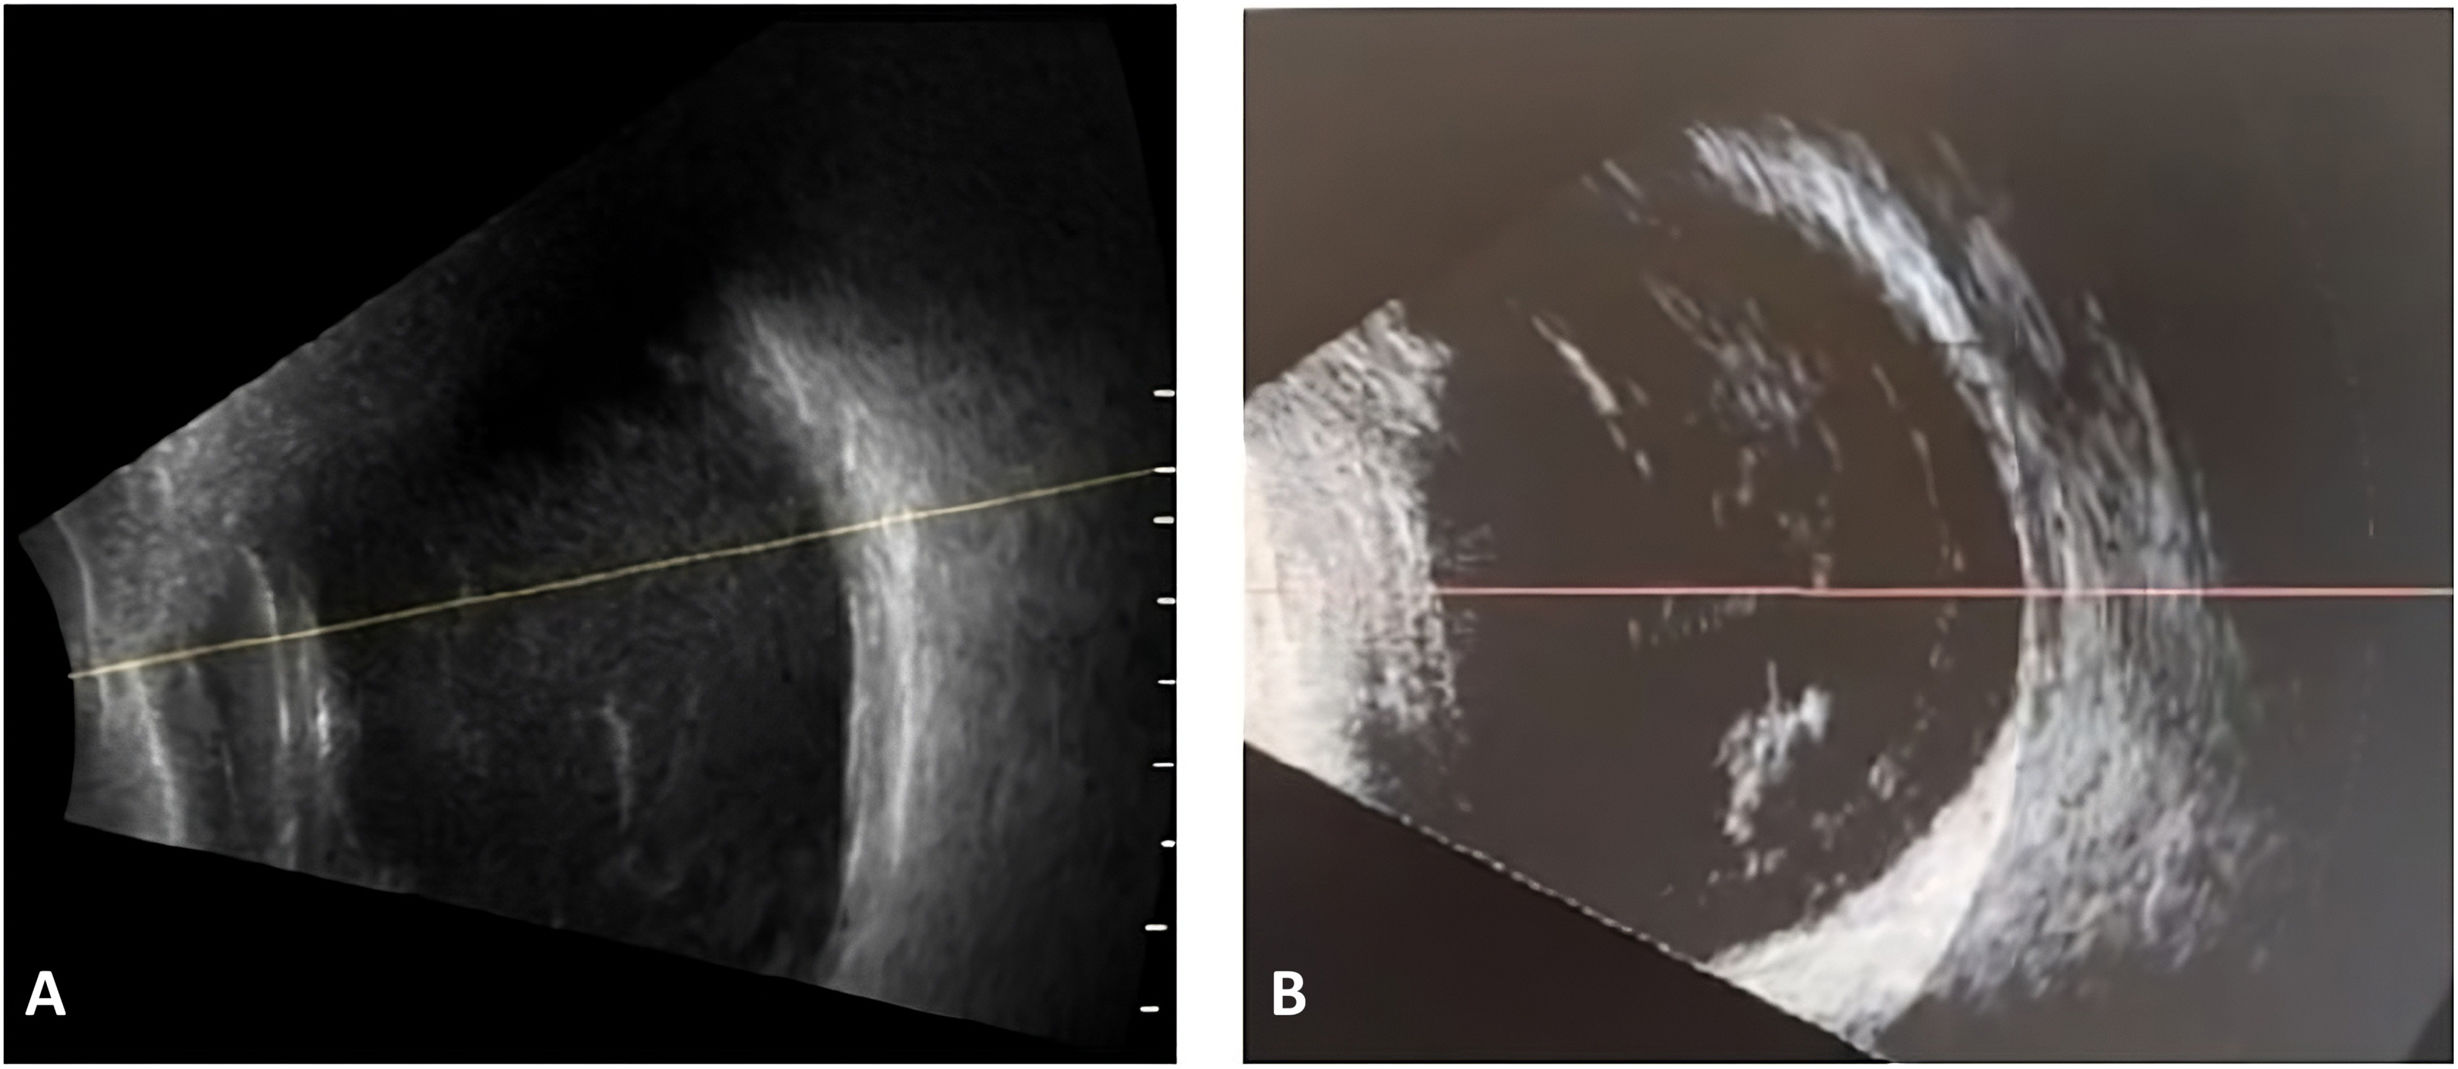

La ecografía ocular en modo B mostró densas condensaciones vítreas móviles en forma de membranas, sin punteado fino difuso (fig. 1). Se inició tratamiento empírico para endoftalmitis infecciosa con vancomicina (1mg/0,1ml) y ceftazidima (2mg/0,1ml) intravítreas, tras la toma de muestra de humor acuoso para estudio microbiológico, que resultó negativo. Se indicó ciprofloxacina oral y prednisolona tópica, sin añadir colirios antibióticos reforzados, conforme a las recomendaciones para el manejo inicial ante la sospecha de endoftalmitis.

Comparación del patrón ecográfico en modo B en 2 casos de inflamación intraocular con ocupación vítrea. A) Endoftalmitis bacteriana confirmada tras Ozurdex®, mostrando ocupación vítrea difusa, múltiples puntos hiperecogénicos e imágenes de membrana. B) Endoftalmitis estéril (caso propio) con bandas vítreas densas, móviles y organizadas, intercaladas con espacios anecoicos.

El hallazgo más distintivo fue la apariencia anómala del implante —edematizado y rodeado de sábanas vítreas—, diferente de las complicaciones clásicas de Ozurdex® y de las imágenes ecográficas típicas de vitritis infecciosa (figs. 1 y 2), sugiriendo una alteración de su cápsula polimérica, con posible liberación acelerada de dexametasona o de polímeros (PLGA), desencadenando una reacción inflamatoria intensa de tipo irritativo o inmunológico3–5. Estos hallazgos apoyan una inflamación directamente relacionada con el implante y no con un proceso infeccioso difuso3.